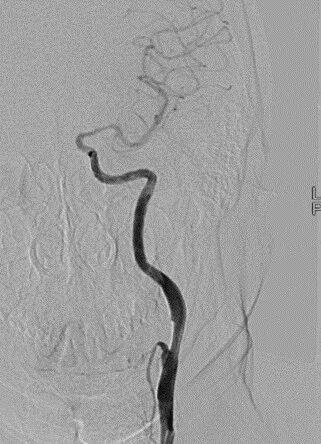

左侧颈内动脉起始段重度狭窄。

波科支架怎么样径技-弓上病例大赏|第205期·放疗后症状性颈动脉狭窄支架置入治疗一例_https://www.jmylbn.com_新闻资讯_第12张

波科支架怎么样径技-弓上病例大赏|第205期·放疗后症状性颈动脉狭窄支架置入治疗一例_https://www.jmylbn.com_新闻资讯_第13张

波科支架怎么样径技-弓上病例大赏|第205期·放疗后症状性颈动脉狭窄支架置入治疗一例_https://www.jmylbn.com_新闻资讯_第14张